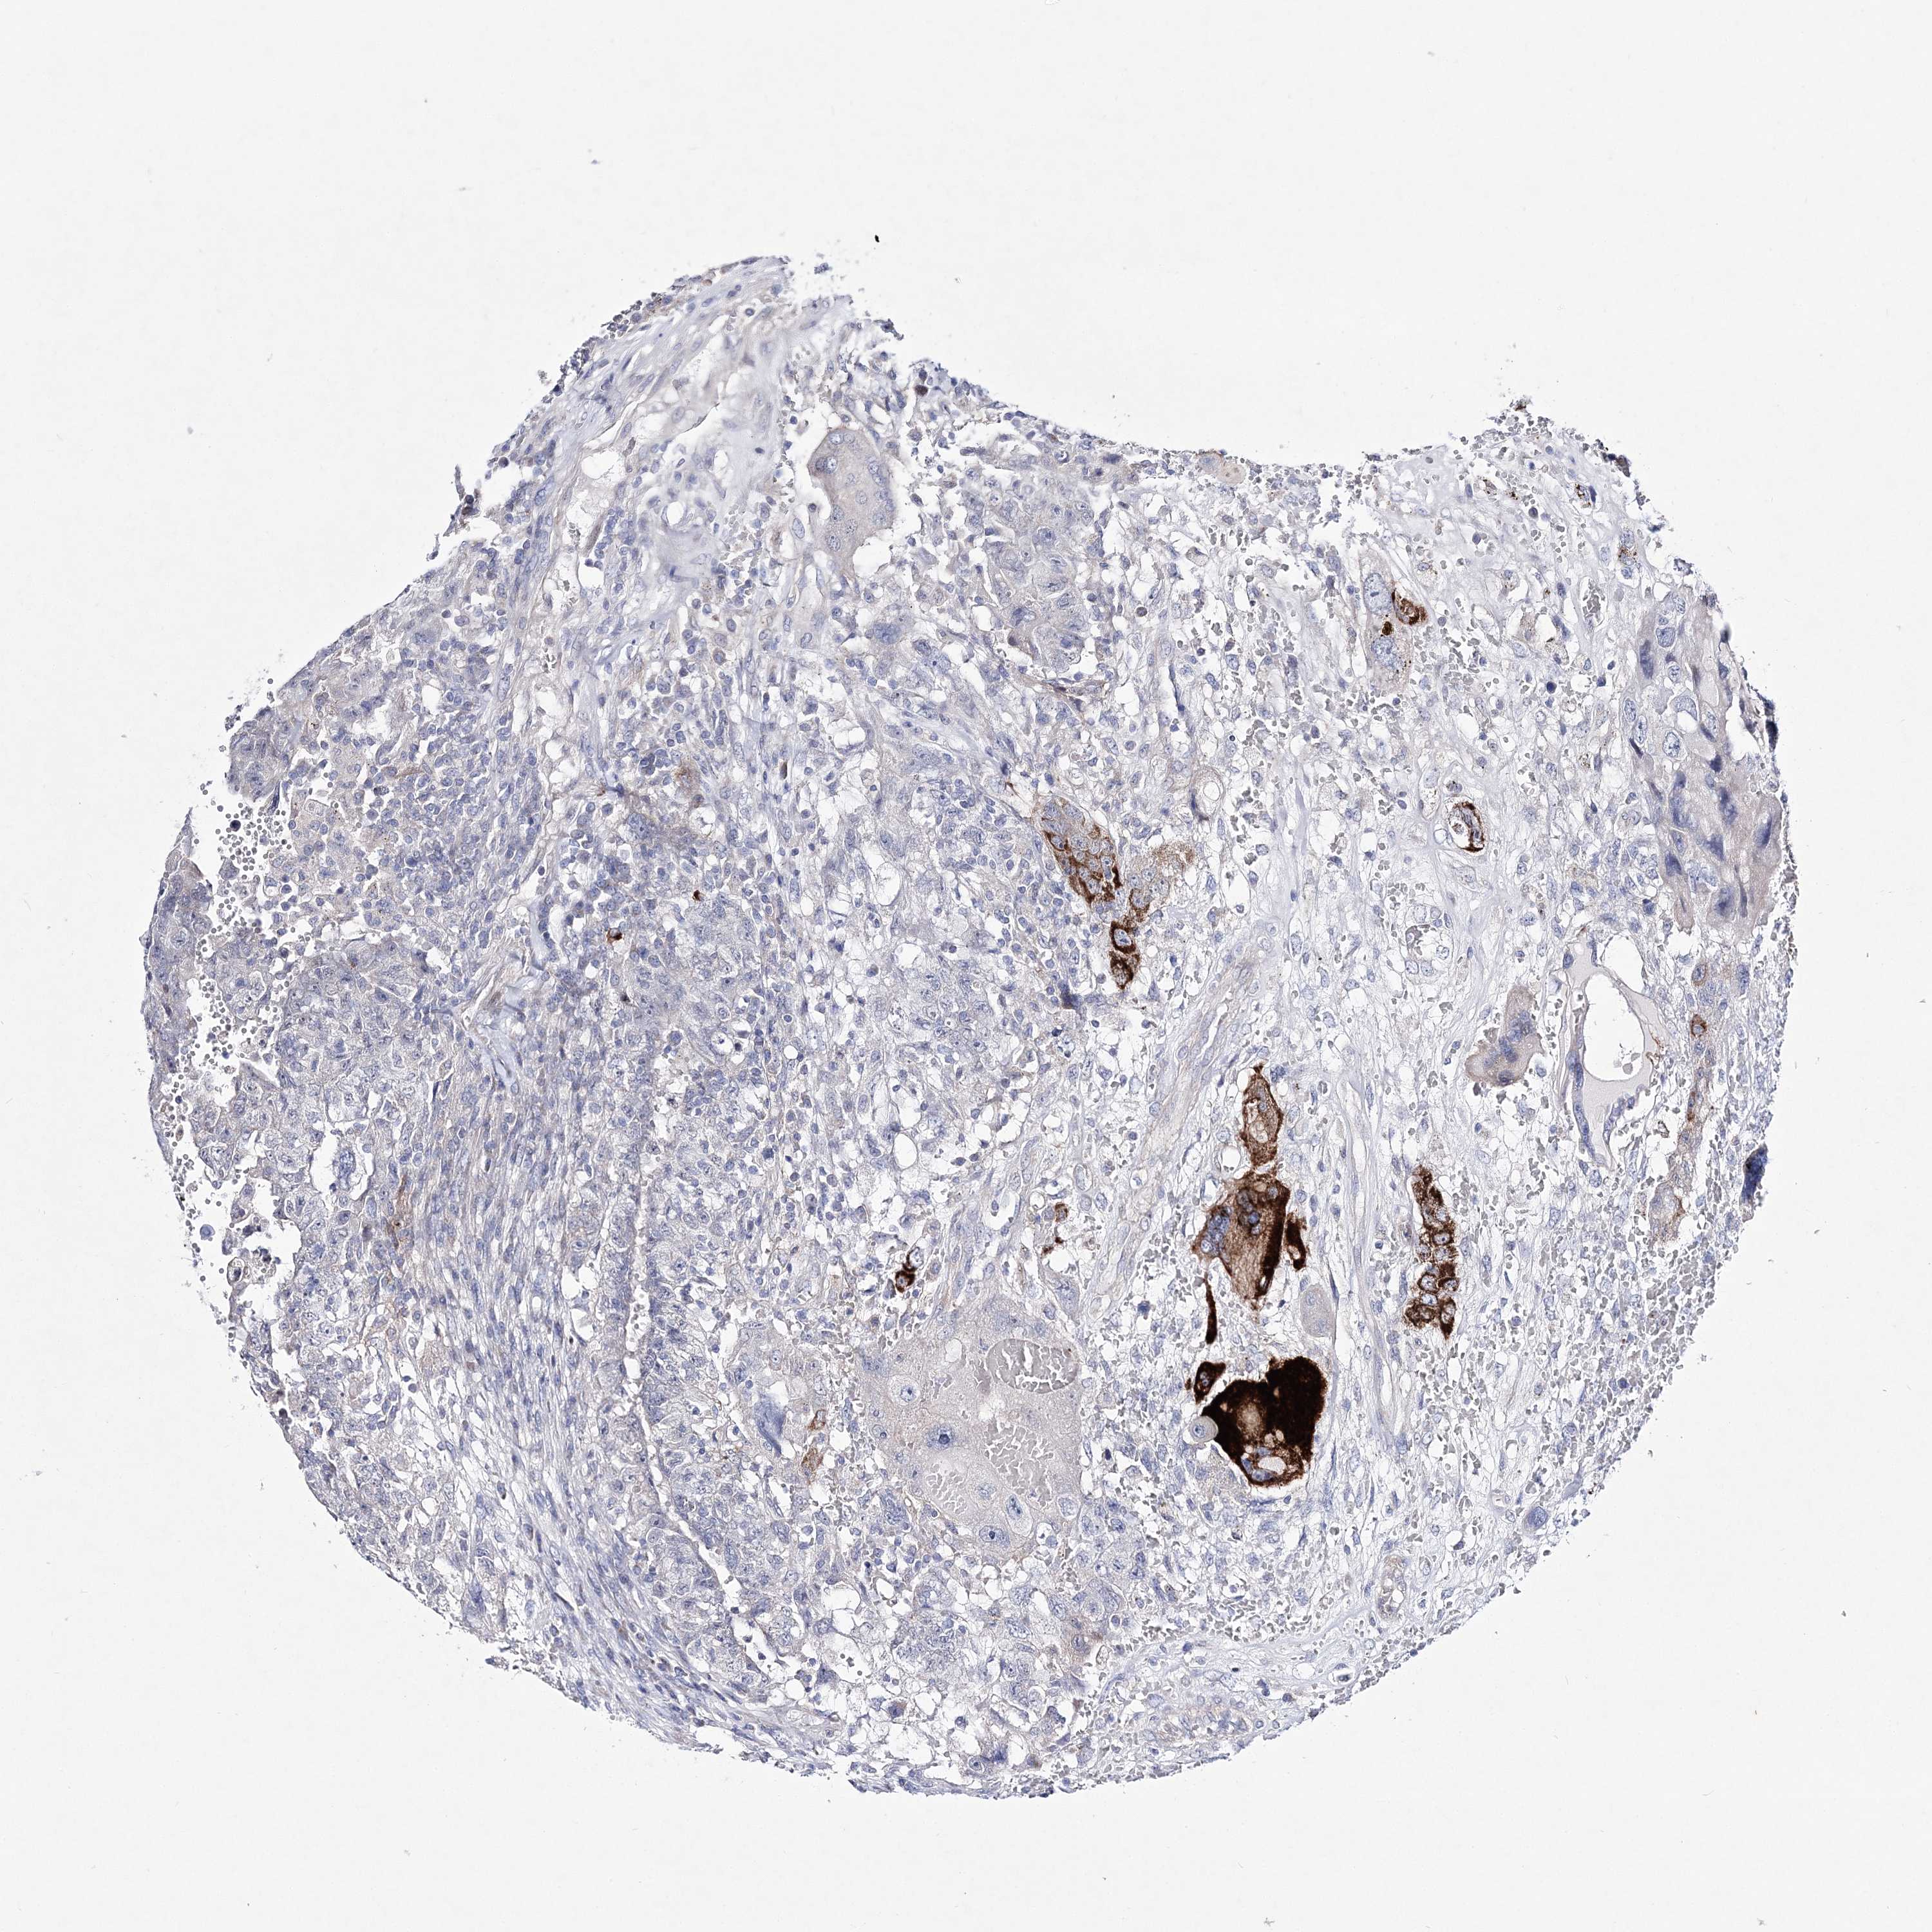

TESTIS CANCER - Protein expressioni

A mouse-over function shows sample information and annotation data. Click on an image to view it in a full screen mode. Samples can be filtered based on level of antibody staining by selecting one or several of the following categories: high, medium, low and not detected. The assay and annotation is described here.

Note that samples used for immunohistochemistry by the Human Protein Atlas do not correspond to samples in the TCGA dataset.

Antibody stainingi

Antibody staining in the annotated cell types in the current human tissue is reported as not detected, low, medium, or high, based on conventional immunohistochemistry profiling in selected tissues. This score is based on the combination of the staining intensity and fraction of stained cells.

Each image is clickable and will lead to virtual microscopy that enables deeper exploration of all samples and also displays staining intensity scores, fraction scores and subcellular localization as well as patient and tissue information for each sample.

Antibody HPA032148

Antibody HPA057356

Carcinoma, Embryonal, NOS

Seminoma, NOS

Teratoma, malignant, NOS